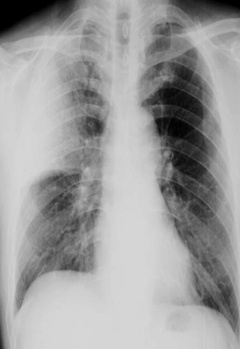

圖中可見右上葉“一片白”,根據(jù)公式診斷為右上葉大葉性肺炎